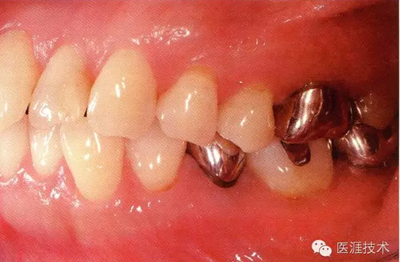

55歲男性抽煙患者(1天20支、抽煙35年)。菌斑控制得不好。通過牙周探診,全頜有4~9mm的牙周袋,有1~3度的根分叉部病變。通過X光片觀察,上頜前牙中度牙槽骨吸收,其他地方有中度牙槽骨吸收。受吸煙影響,牙齦纖維性肥厚,呈紅黑色。牙齦幾乎沒有浮腫和發(fā)紅,所以這個病例是從外觀上無法預(yù)測病癥嚴重程度的病例。